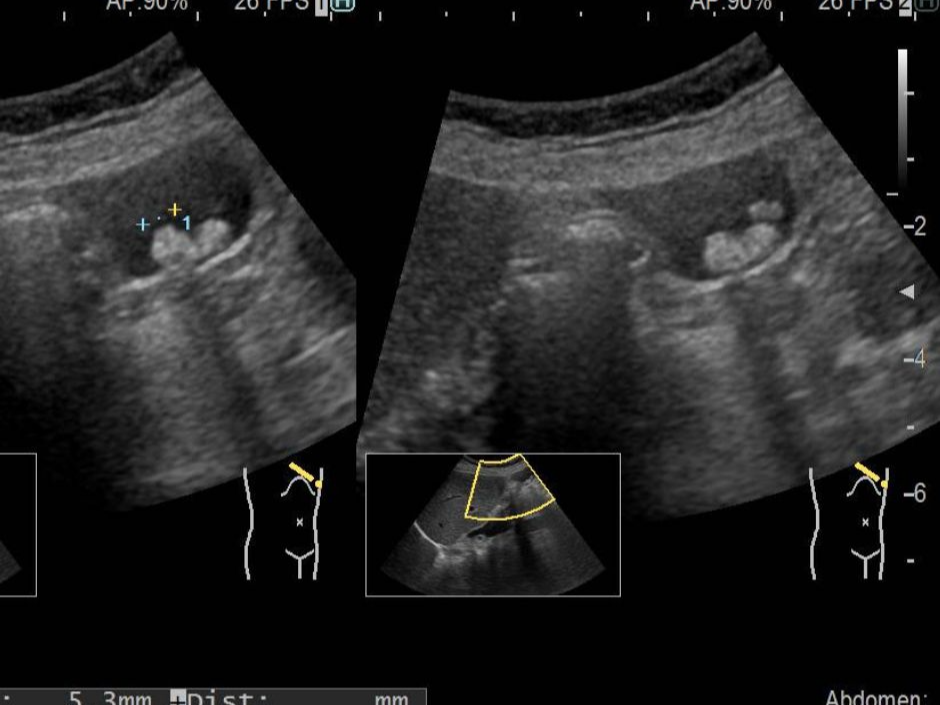

담석증은 간에서 생성된 담즙이 저장되는 담낭 또는 담관에서 결석이 형성되는 질환입니다. 담즙은 지방 소화를 돕는 중요한 역할을 하지만, 특정 조건에서 성분이 굳어지면서 돌 형태로 변하게 됩니다. 담석은 크기와 개수가 다양하며, 증상이 없는 경우도 있지만 특정 상황에서는 심한 통증과 염증을 유발합니다.

담석증은 초기에는 무증상인 경우가 많지만, 담석이 담관을 막거나 염증을 유발하면 다양한 증상이 나타납니다.

통증의 위치와 강도가 특징적이며, 특정 상황에서 반복적으로 발생하는 경향이 있습니다.